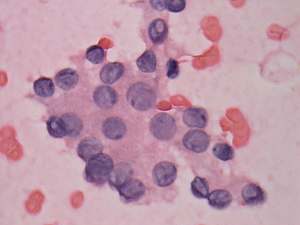

Cytology. Papillary cancer was diagnosed in the nodule in the left lobe and a metastasis of the thyroid cancer into one of the enlarged lymph nodes.

Histopathology. Papillary cancer in the left lobe with metastasis to the lymph nodes, and hyperplastic nodules in the right lobe.